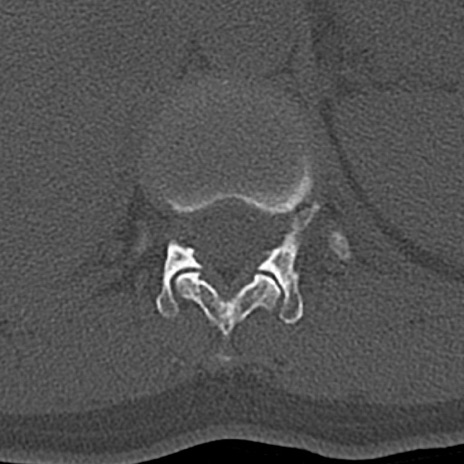

【整形】TIPS症例4 腰椎CT(横断像)

腰椎CT

横断像と矢状断像